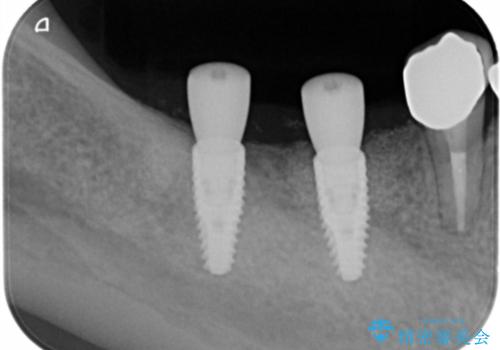

X線写真検査より、クラウンや銀歯の下で歯に大きな虫歯が発生し、抜歯を余儀なくされる状況でした。

虫歯に伴い歯槽骨の吸収も見られたので造骨後、インプラントを用いて咬合機能を回復します。

- 110万円(インプラント×2・チタンカスタムアバットメント×2・ジルコニアクラウン×2・仮歯×2・遊離歯肉移植術)費用は治療当時の料金となります